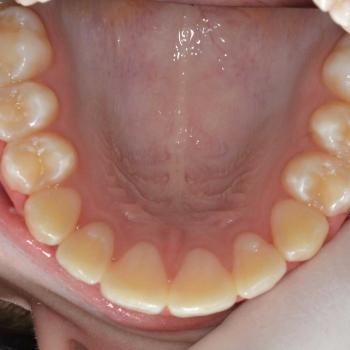

Kíra és édesanyja egy kollegám javaslatára kerestek fel a rögzített fogszabályzó számára legoptimálisabb időszakban, a tejfogak leváltása után, de még a 7-es fog előtörése előtt. Az első konzultáció alkalmával fény derült az alsó és felső fogív nagymértékű torlódására, a jobb felső szemfog kiszorult helyzetére és következményes felső középvonal eltolódására, illetve az enyhe mélyharapásra. A röntgenek kiértékelése után ez a kórkép kiegészült az alsó és felső metszőfogak hátradőlt pozíciójával, ami a kezelést nagyban megkönnyítette, mert lehetőséget adott mindkét fogív meghosszabbítására, így helynyerésre a torlódott fogazat számára.

Ennek megfelelően a kezelés kizárólag alsó és felső hagyományos fém fogszabályozót tartalmazott bite turbo harapásemeléssel kiegészítve, illetve a harapás finombeállításához különböző intermaxilláris gumihúzásokkal.